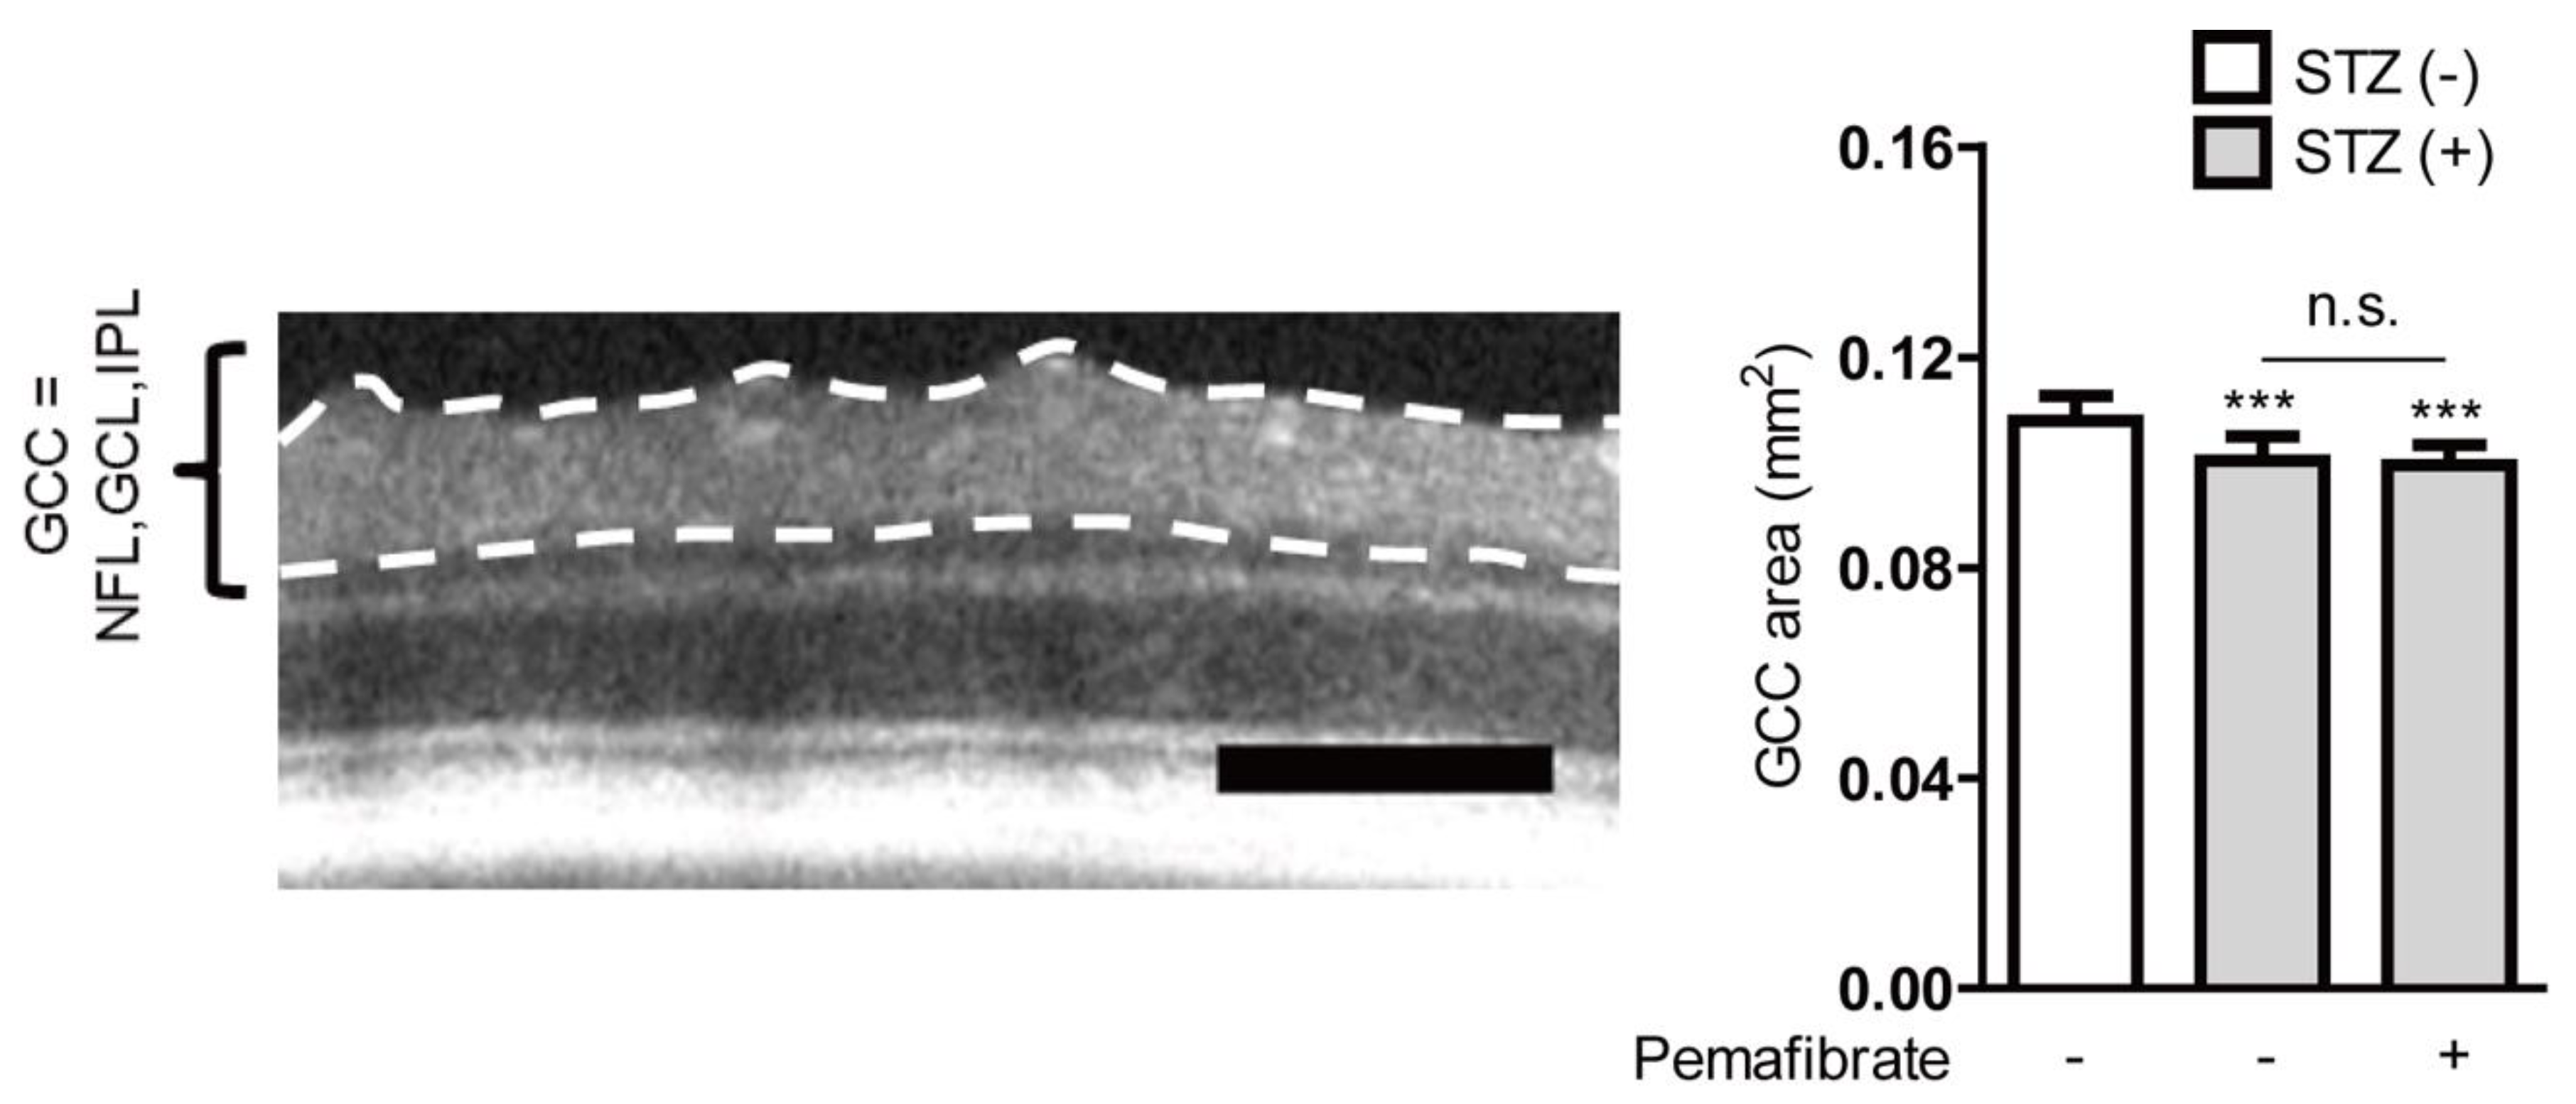

4.9. Optical Coherence Tomography (OCT)

- Sergeys, J.; Etienne, I.; Van Hove, I.; Lefevere, E.; Stalmans, I.; Feyen, J.H.M.; Moons, L.; Van Bergen, T. Longitudinal In Vivo Characterization of the Streptozotocin-Induced Diabetic Mouse Model: Focus on Early Inner Retinal Responses. Investig. Ophtalmol. Vis. Sci. 2019, 60, 807–822. [Google Scholar] [CrossRef] [PubMed]

- van Dijk, H.W.; Verbraak, F.D.; Kok, P.H.B.; Stehouwer, M.; Garvin, M.K.; Sonka, M.; DeVries, J.H.; Schlingemann, R.O.; Abràmoff, M.D. Early neurodegeneration in the retina of type 2 diabetic patients. Investig. Ophtalmol. Vis. Sci. 2012, 53, 2715–2719. [Google Scholar] [CrossRef]

- van Dijk, H.W.; Kok, P.H.; Garvin, M.; Sonka, M.; Devries, J.H.; Michels, R.P.; van Velthoven, M.E.; Schlingemann, R.O.; Verbraak, F.D.; Abràmoff, M.D. Selective loss of inner retinal layer thickness in type 1 diabetic patients with minimal diabetic retinopathy. Investig. Ophtalmol. Vis. Sci. 2009, 50, 3404–3409. [Google Scholar] [CrossRef] [PubMed]